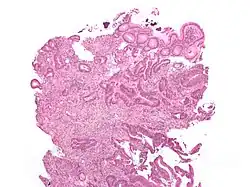

Micrograph showing sodium polystyrene sulfonate crystals (purple – at top of the image) in the biopsy of a colonic mass. H&E stain.

Polystyrene sulfonate is usually supplied in either the sodium or calcium form. It is used as a potassium binder in acute and chronic kidney disease for people with hyperkalemia (an abnormally high blood serum potassium level).[3] However, it is unclear if it is beneficial and there is concern about possible side effects when it is combined with sorbitol.[4]